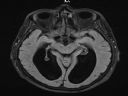

macie moze jakis pomysl co jest nie tak na tym zdjeciu? --->

toaster <--- przeciez to nie moja glowa :D staram sie tylko zdobyc bonusowe punkty w kole neurochirurgii ale jestem dopeiro na I roku i nie zaczelismy jeszcze w ogole przerabiac osrodkowego ukladu nerwowego ^^

Widzę dwie czarne (puste?) przestrzenie na obu półkulach.